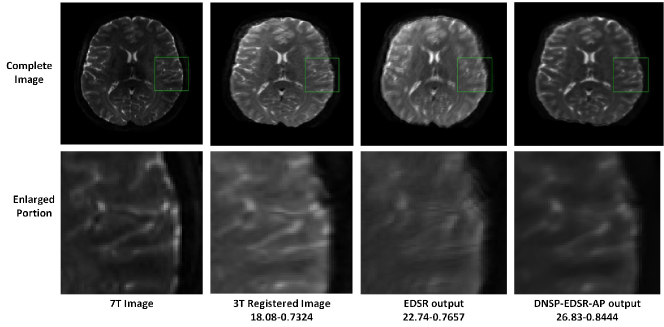

Figure 2: An example that demonstrates that MR brain images are naturally rank deficient. The low rank images are obtained by zeroing out the smallest singular values (from the SVD). This example reveals that the image has an effective rank in the range 115-120.

Low Rank Prior: It has been demonstrated recently [30, 38, 9, 39] that MR images are naturally rank deficient. For example, Figure 2 shows several low rank images of an MR image reconstructed from partial singular value decomposition (SVD) approximation. We can observe that the recovered image with a rank of 90, which is approximately half of full rank (170) of the image matrix; still exhibits a Peak Signal to Noise Ratio (PSNR) of about 45dB. Further, the reconstruction is visually indistinguishable from the original image. We wish to emphasize that an image being low-rank implies that the effective rank of the matrix is low. For example, it can be observed from Figure 2 that the change in PSNR value in the range of 110-120 rank is relatively negligible compared to that of the PSNR change in the range of 90-110 rank. Hence the effective rank of this particular image can be argued to be in between 115 and 120 which is much smaller than the full rank of 170. Rank of an image captures the global structure of a given image. An effective low-rank implies that the image adheres to some structural properties like near symmetry which can be observed in brain images. Hence, a low-rank constraint is effective in recovering the global structure of a given brain image.

Refer to caption

Figure 19: Comparisons of EDSR and DNSP-EDSR-AP on 3T7T-DW dataset [48]. The numerical assessment is shown as PSNR-SSIM. The DNSP-EDSR generates the best results both numerically and visually compared to EDSR for 3T7T-DW dataset.